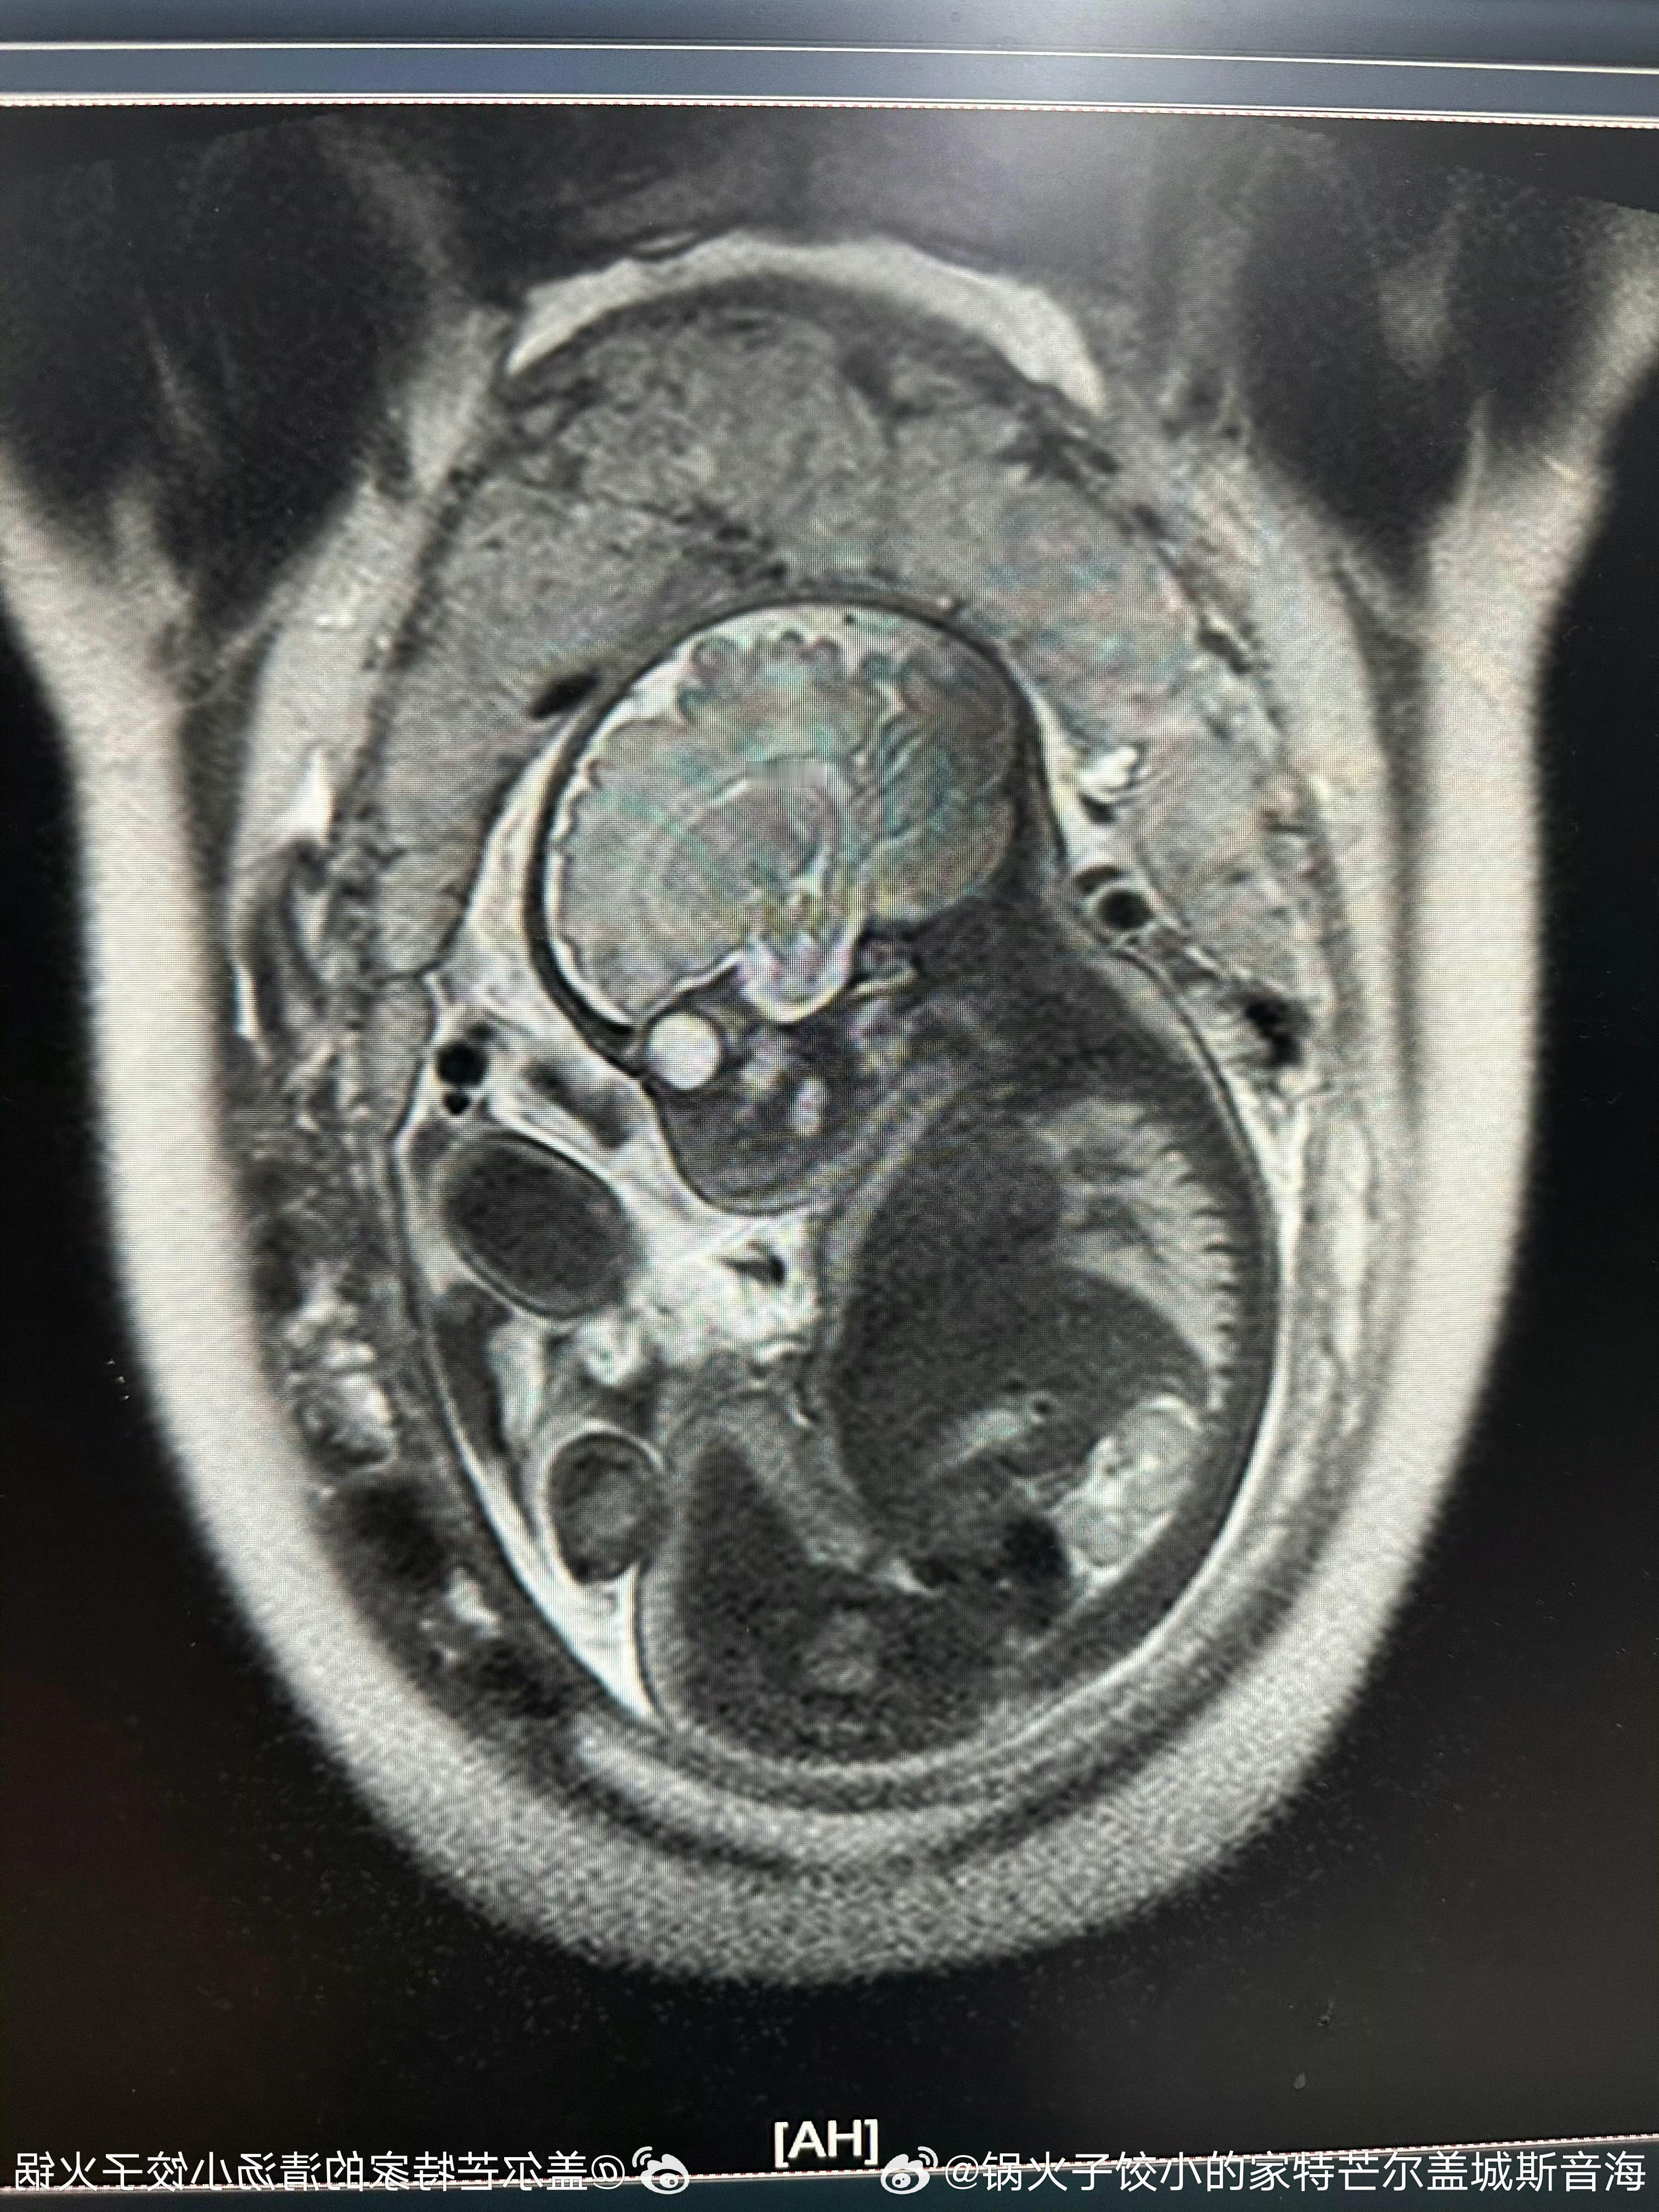

10:31 02˙21˙3202儿孩男小个是还!爱可多,宝宝小的下磁核